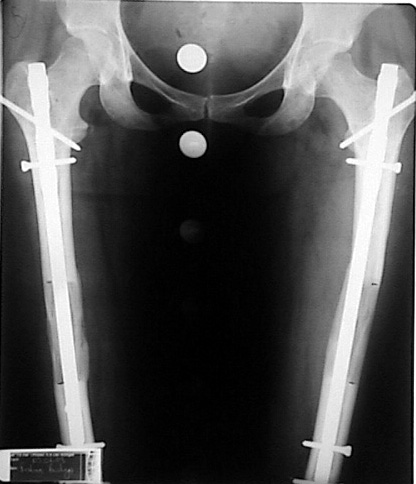

The application of the external fixator: Three Schanz screws are placed distally and three screws are placed proximally. At least 1 mm of distance shall remain between the screws and the nail.

Postoperative care: Distraction is commenced at day 10. 0,25 mm of lengthening is perfomed 4 times daily (every 6 hours). Hip and knee joint motion exercises begin at 1-2. day postoperatively. For many years, the treatment of lower extremity shortness has been very hard for the patient and the surgeon. The techniques developed after the introduction of Ilizarov’s distraction osteogenesis concept have pioneered a new era, and have been considered to be procedures in which previous complications are encountered much less frequently.

In selected cases, we prefer to use a combination of a unilateral dynamic axial fixator and an interlocked intramedullary nail, in order to protect the length and alignment after the completion of the lengthening procedure. As a prerequisite for this technique, the narowest diameter of the medullary cavity shall be wider than 7 mm and the length of the nail segment distal to the osteotomy site shall be at least 8 cm. after the completion of the lengthening procedure.The intramedullary nail neutralizes shear and bending forces on femur during lengthening, shortens external fixation time, and protects newly formed bone against fractures. In our series, subtrochanteric osteotomy was performed in one case. No varus angulation occured despite the intramedullary nail.

Ilizarov stressed the significance of endosteal blood circulation for distraction osteogenesis. Although we placed the intramedullary nail after reaming the femur in all cases, the time for callus formation was not longer than expected. Thus we found that there is no slowing in the rate of new bone formation due to disruption of medullary blood flow. The rationale of this finding is revascularization that occurs following reaming of the medullary cavity, the fixation stability with the intramedullary nail and early functional weight bearing. The potential disadvantages of a combined use of external and internal fixation metods are increased blood loss, intramedullary infection, risk of fat embolism and excessive metal load.The most fearsome complication is a deep intramedullary infection (panosteomyelitis) triggered by pin tract infection.No such complication was encountered in our series. In order to avoid this complication, after the completion of lengthening the nail shaill be interlocked from the medial side, and contact of internal and external fixator pins shall be avoided.